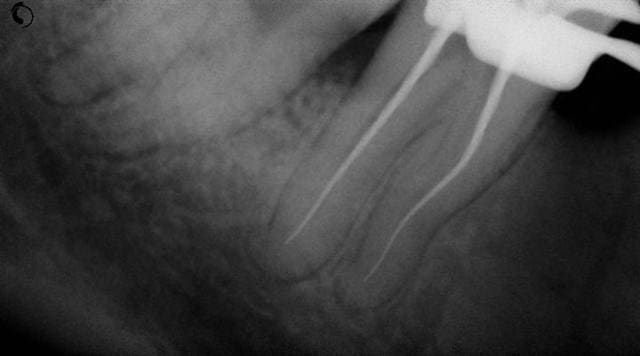

Dernièrement, je me suis retrouvé confronté à une 47 dont les racines sont relativement tourmentées. (voir radios) Je me suis alors trouvé dans l'impossibilité d'aleser le dernier mm. J'ai utilisé des limes manuelles de diamètre 08, 10 et 15, des protapers neufs en démarrant par le violet, et toujours le même problème. il me manque 1 mm.

Elles sont plus que tourmentées...

sur la radio préop, on voit nettement le crochet apical qui part en distal. Vu la double courbure, il était difficile de pouvoir atteindre ce crochet. A l'impossible, nul n'est tenu.